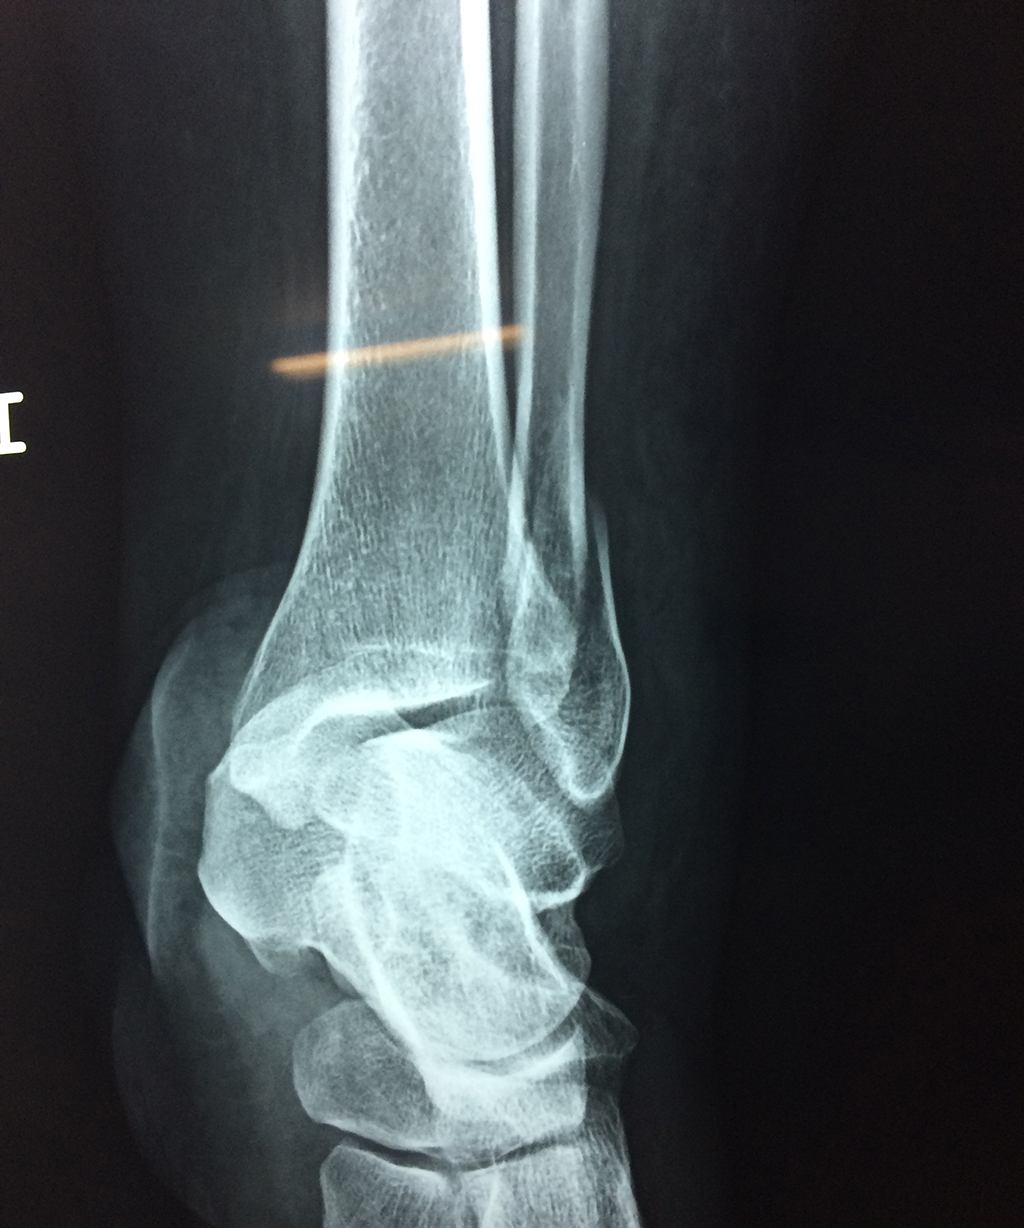

Una fractura de tobillo es la rotura de uno o más de los huesos del tobillo. Estas fracturas pueden ser:

- Completas (el hueso está perforado y está en 2 partes).

- Los extremos de los huesos están desalineados entre sí (desplazados).

- La fractura se extiende hasta la articulación del tobillo (fractura intra-articular).